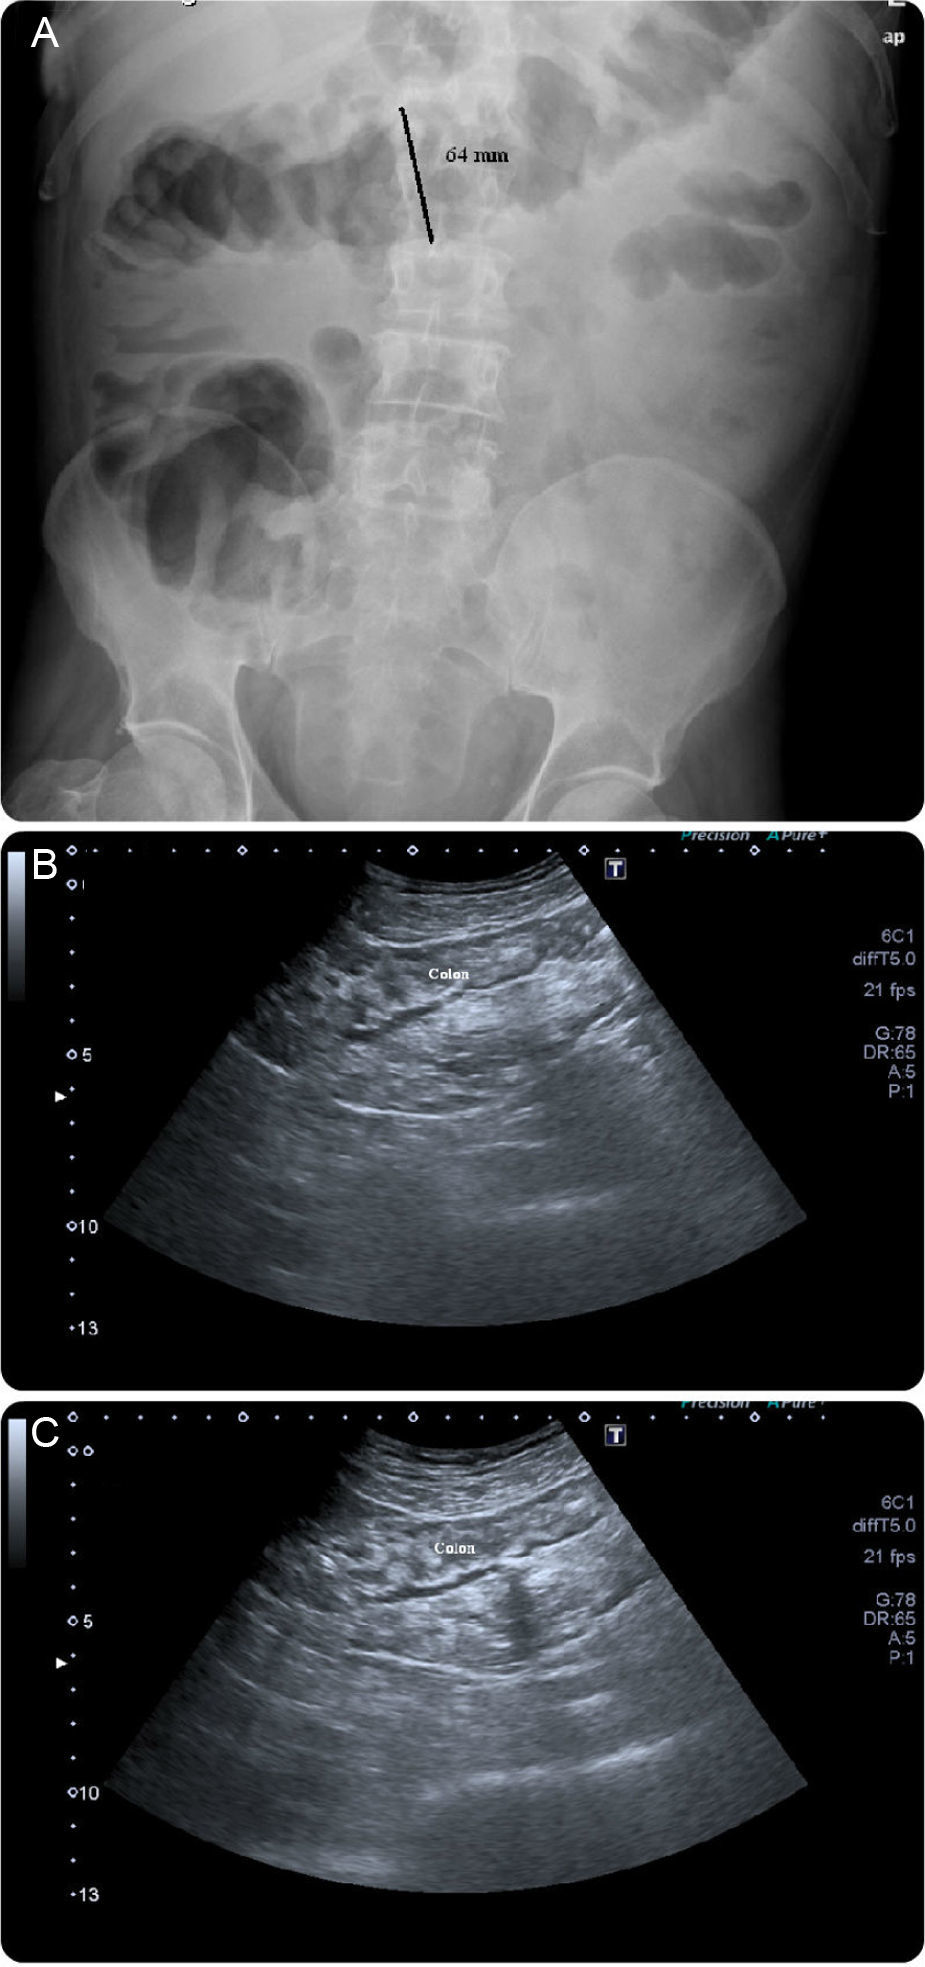

A case of a 62-year-old man with a retroauricular melanoma is reported, in whom it was decided to initiate ipilimumab as second-line chemotherapy (after tumor progression with conventional first-line chemoradiation therapy). Twenty-four hours after first infusion, the patient reported a diffuse abdominal pain and a mild bloody diarrhea (3–4 bloody stools/day). Two days after a second scheduled administration, fever (38–39°C) and vomiting were added to the previous symptoms. At this point, it was decided to withdraw ipilimumab and the patient was given loperamide and reinforced oral hydration. Despite these measures, the patient remained symptomatic leading to an admission in our ward. At presentation he was febrile (38.9°C), hemodynamically stable, moderately dehydrated and in the abdominal examination he had a localized tenderness in the left iliac fossa. The laboratory results showed no anemia ([Hb]=14g/dL), no leukocytosis but a markedly elevated C-reactive protein (20mg/dL; reference value:<0.5mg/dL). Standard stool examinations for bacteria, Clostridium difficile (toxin), ova, cysts and parasites were negative. On using plain abdominal radiograph and abdominal ultrasound (US) no sign of perforation or collection was noticed. Following a discussion with his assistant oncologist it was decided to start intravenous steroids (prednisolone 40mg/day). After seven days of treatment the symptoms improved significantly and the patient was discharged with 20mg of prednisolone/day per os. Seventy-two hours after discharge, the patient returned to our clinic complaining about an increase in the bloody stool frequency (7–10 per day). At that time, he was hypotensive, normocardic and afebrile. Remaining physical examination was unremarkable. It was decided to reinstitute prednisolone at a dose of 40mg/day, intravenously. Despite those measures, symptoms were refractory and the bloody diarrhea did not resolve so fast has it was expected to. On the seventh day of treatment, the patient had a massive hematochezia, with [Hb] drop (to 9g/dL) and C-reactive protein rouse (30mg/dL). Plain abdominal radiographs (Fig. 1A) showed a dilated transverse colon (with a diameter of 64mm) consistent with a megacolon by radiological criteria. Abdominal US showed no intra-abdominal complications, revealing only a slight thickening of the sigmoid wall (5–6mm; Fig. 1B and C). A left colonoscopy was performed (Fig. 2), demonstrating a patchy but extensive and deep ulceration of the left colon, from the splenic flexure until the sigmoid colon, sparing the rectum. The ulcers were covered with exudates and fresh blood. Histological findings were non-specific, demonstrating a mixed inflammatory component (with a lymphoplasmocytic infiltrate of B and T cells), lymphoid aggregates and eosinophils, extensive ulceration and granulation tissue. On the base of the ulcerated tissue, aspects of fibrinoid necrosis of the vessels wall and fibrin clots were visible. Immunohistochemistry excluded the presence of cytomegalovirus inclusions. Broad spectrum antibiotics were promptly initiated and steroid therapy was optimized to 100mg/day intravenously (prednisolone 1.5mg/Kg/day). After 5 days, there was a significant clinical improvement, the patient had less than 3 bowel movements/day (without blood), no abdominal pain and was afebrile. Laboratory tests revealed a marked decrease in C-reactive protein (3.7mg/dL), no leukocytosis and a stable [Hb] (10.8g/dL). After ten additional days, the patient was discharged, medicated with 100mg/day of prednisolone per os followed by a slow weaning course (lasting 8 weeks). Ipilimumab was permanently withdrawn and the patient remains asymptomatic after steroid stoppage.